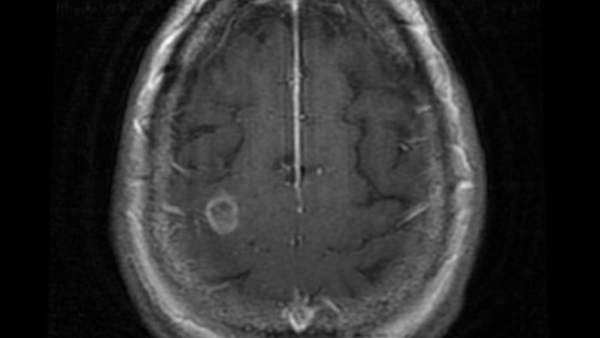

Tras contraer la rara enfermedad fue trasladado al Instituto Nacional de Enfermedades Infantiles (NÚDCH) en Bratislava, donde se le diagnosticó una meningoencefalitis amebiana primaria (PAM), causada por la ameba Naegleria fowleri.